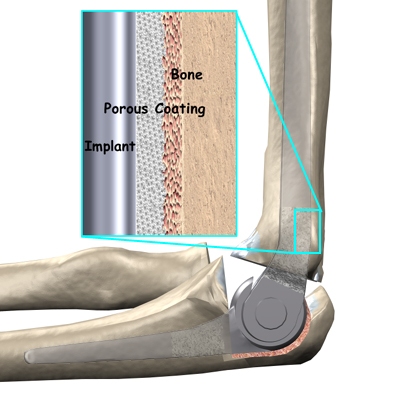

There are two different ways to hold the artificial elbow in place. A uses a special type of epoxy cement to glue it to the bone. The has a fine mesh of holes on the surface. Over time, the bone grows into the mesh, anchoring the prosthesis to the bone.

X-rays will be taken several times after your surgery to make sure that the artificial joint has not moved out of place and that the fusion between the fibula and the tibia is forming. When the uncemented type of implant is used, X-rays also help determine whether bone is attaching to the metal implant.